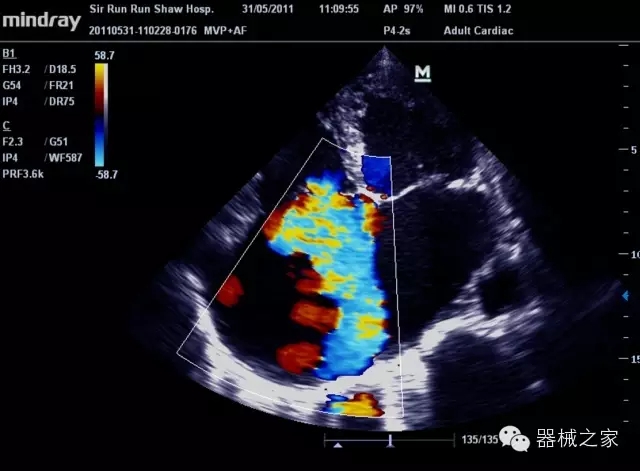

經(jīng)典產(chǎn)品:M7(星鉆)

臨床圖片賞析

產(chǎn)品特點(diǎn)

·裝載有采用Multi-Core多核處理的非嵌入式平臺,成像效率大大提高,并且能夠給用戶帶來高速、多任務(wù)并行信號處理體驗(yàn);

·優(yōu)秀的圖像效果、強(qiáng)大的功能體驗(yàn)、豐富的探頭選擇、合理的便攜式設(shè)計(jì),全中文顯示及病人管理界面,使得M7在任何場合、任何時(shí)候都能快速響應(yīng)更好的心血管、腹部、婦產(chǎn)、小器官等常規(guī)超聲檢查以及肌骨、神經(jīng)、顱腦、術(shù)中等新興領(lǐng)域的使用需求;

8倍波束并行處理系統(tǒng)

·在便攜式緊湊平臺上采用更多倍波束并行接收信號處理模式,無論二維還是彩色血流圖像狀態(tài)下,擁有更靈敏的回波頻移捕獲能力,大大提高時(shí)間分辨率,尤其使得心血管表現(xiàn)更為突出;